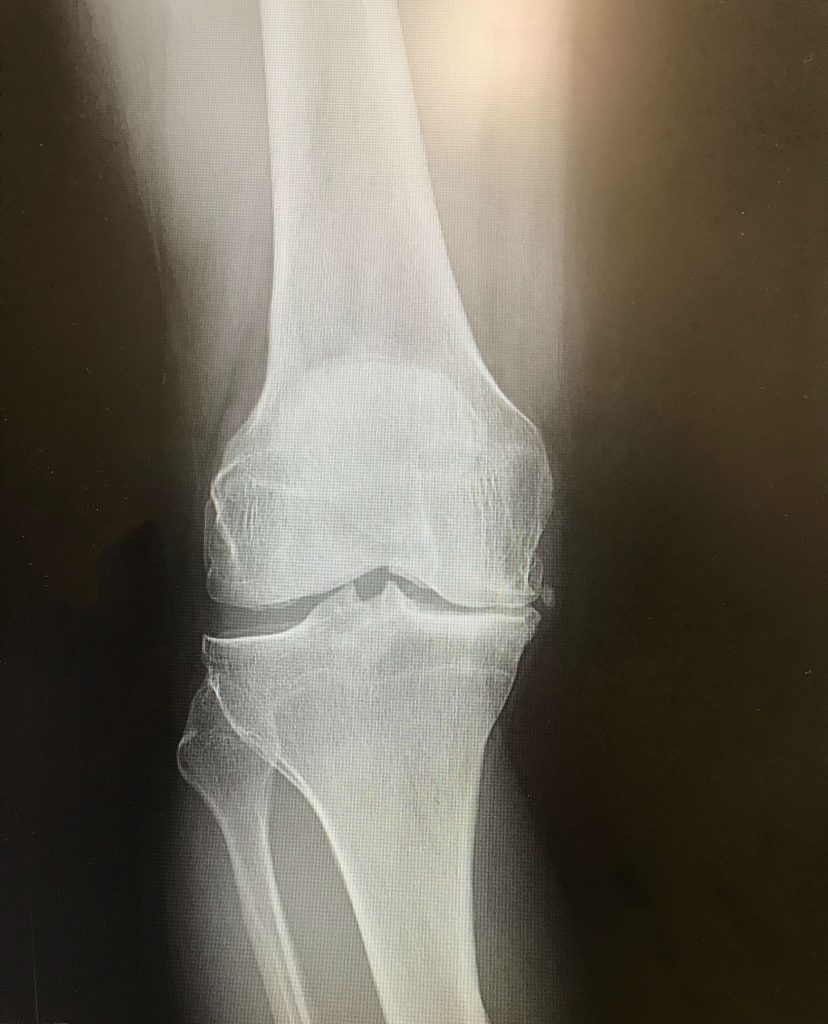

In college I had blown out my ACL. My doctor at the time only cleaned up the injury, but did not repair the ACL. I had continued to be active and even took up running and completed the NYC Marathon. Unfortunately, I had a lot of movement in the knee and this caused my cartilage to deteriorate over the next 30 years. By the time I finally consulted with Dr. DiFelice, he could see a pretty decent amount of bowleggedness due to deteriorated cartilage. He recommended a partial knee replacement and he would try to clean up my damaged ACL. I had the surgery on September 28th. Dr. DiFelice indicated the surgery went well and he was able to tighten up the ACL so my knee would be more stable. I did outpatient physical therapy, bought a Peloton bike and continued at home. I assumed I would have to write off the ski season, but at my December follow up appointment I got the great news that all looked good and I could snowboard! I got in five days with no issues. While I'm not hitting the parks I am able to keep up with friends on black diamond runs! I have had no pain in the knee even though I have snowboarded and become an avid cyclist (including a 41 mile outdoor ride five months post surgery)!